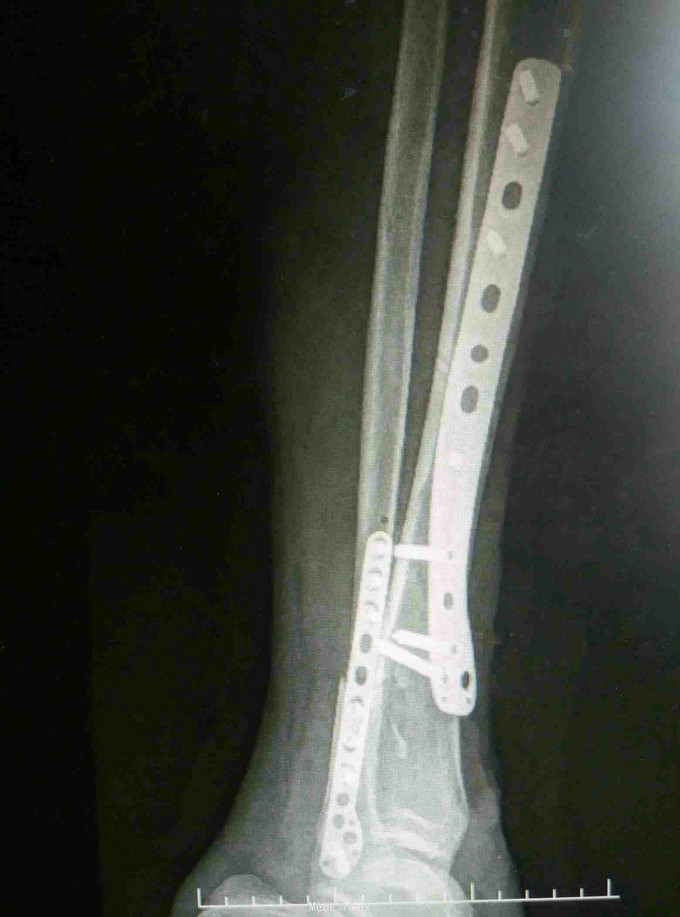

诊断:左胫腓骨远端骨折 治疗:骨折切开复位内固定

讨论:相比上肢尺桡骨双骨折,下肢胫腓骨双骨折更易发生骨筋膜室综合征,应警惕。对胫腓骨碎骨不易过大范围剥离软组织进行复位,以免影响血运得不偿失。